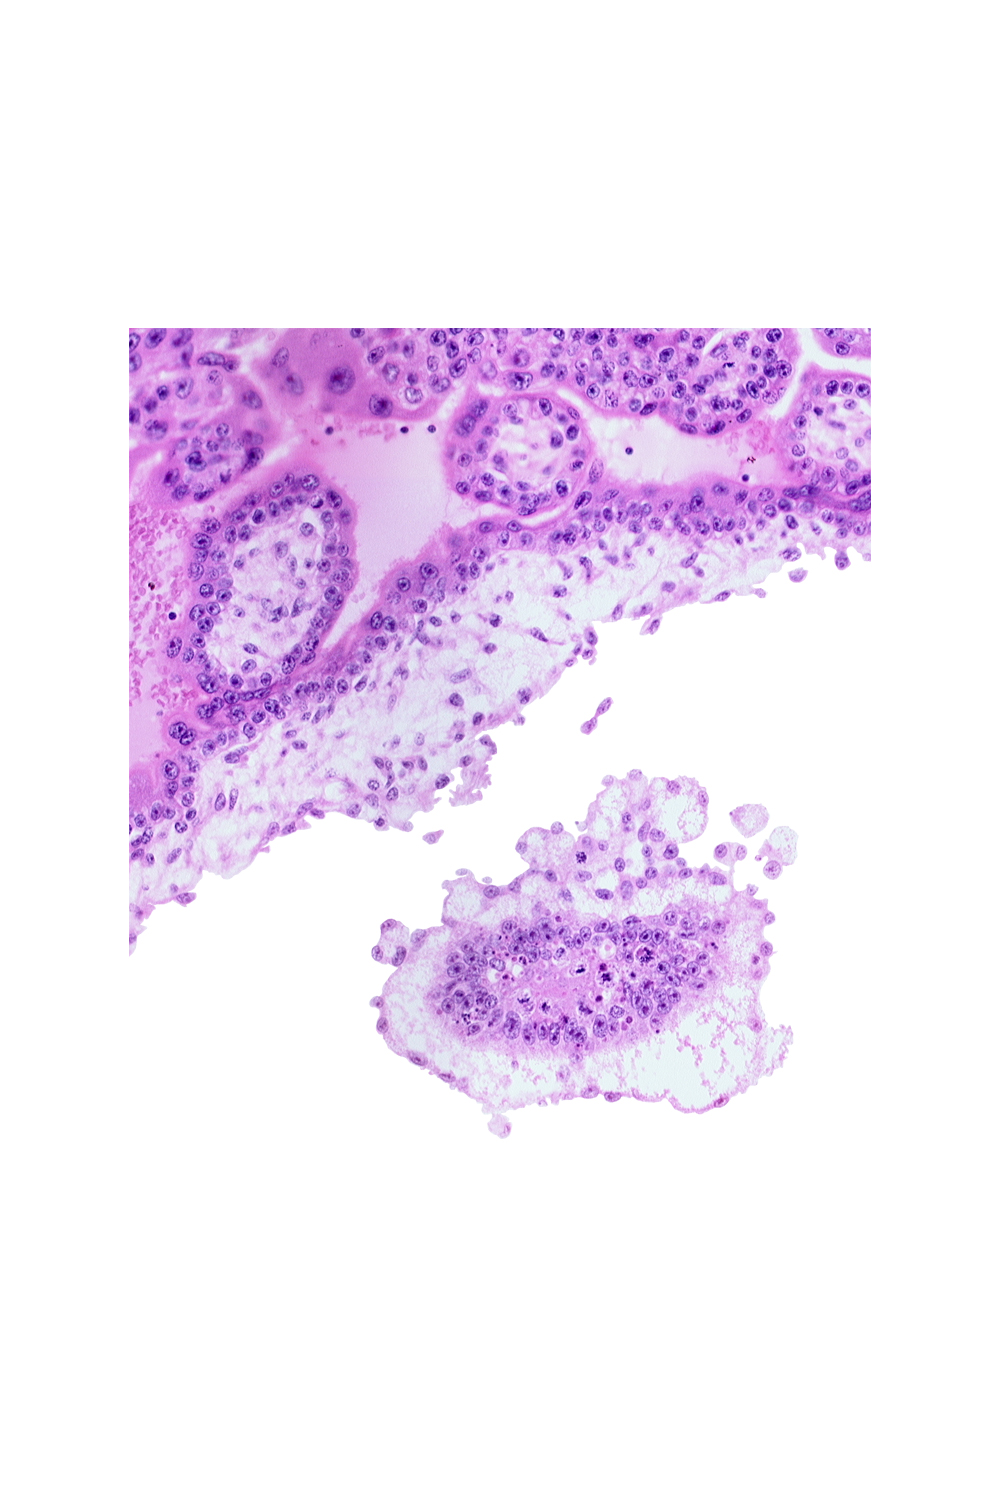

Carnegie Embryo #7802 | Location: 41-03-02

Keywords: cephalic part of embryonic disc, chorionic cavity

Source: The Virtual Human Embryo.